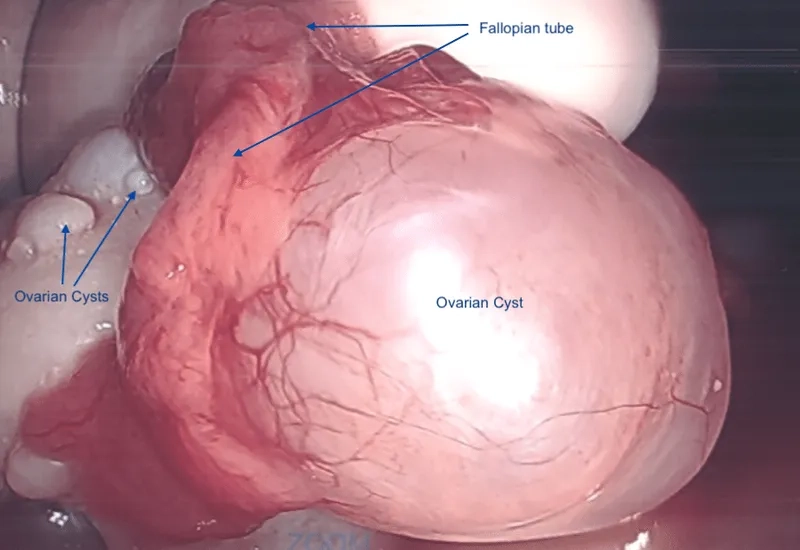

Image illustrating the hormonal effects of Polycystic Ovary Syndrome